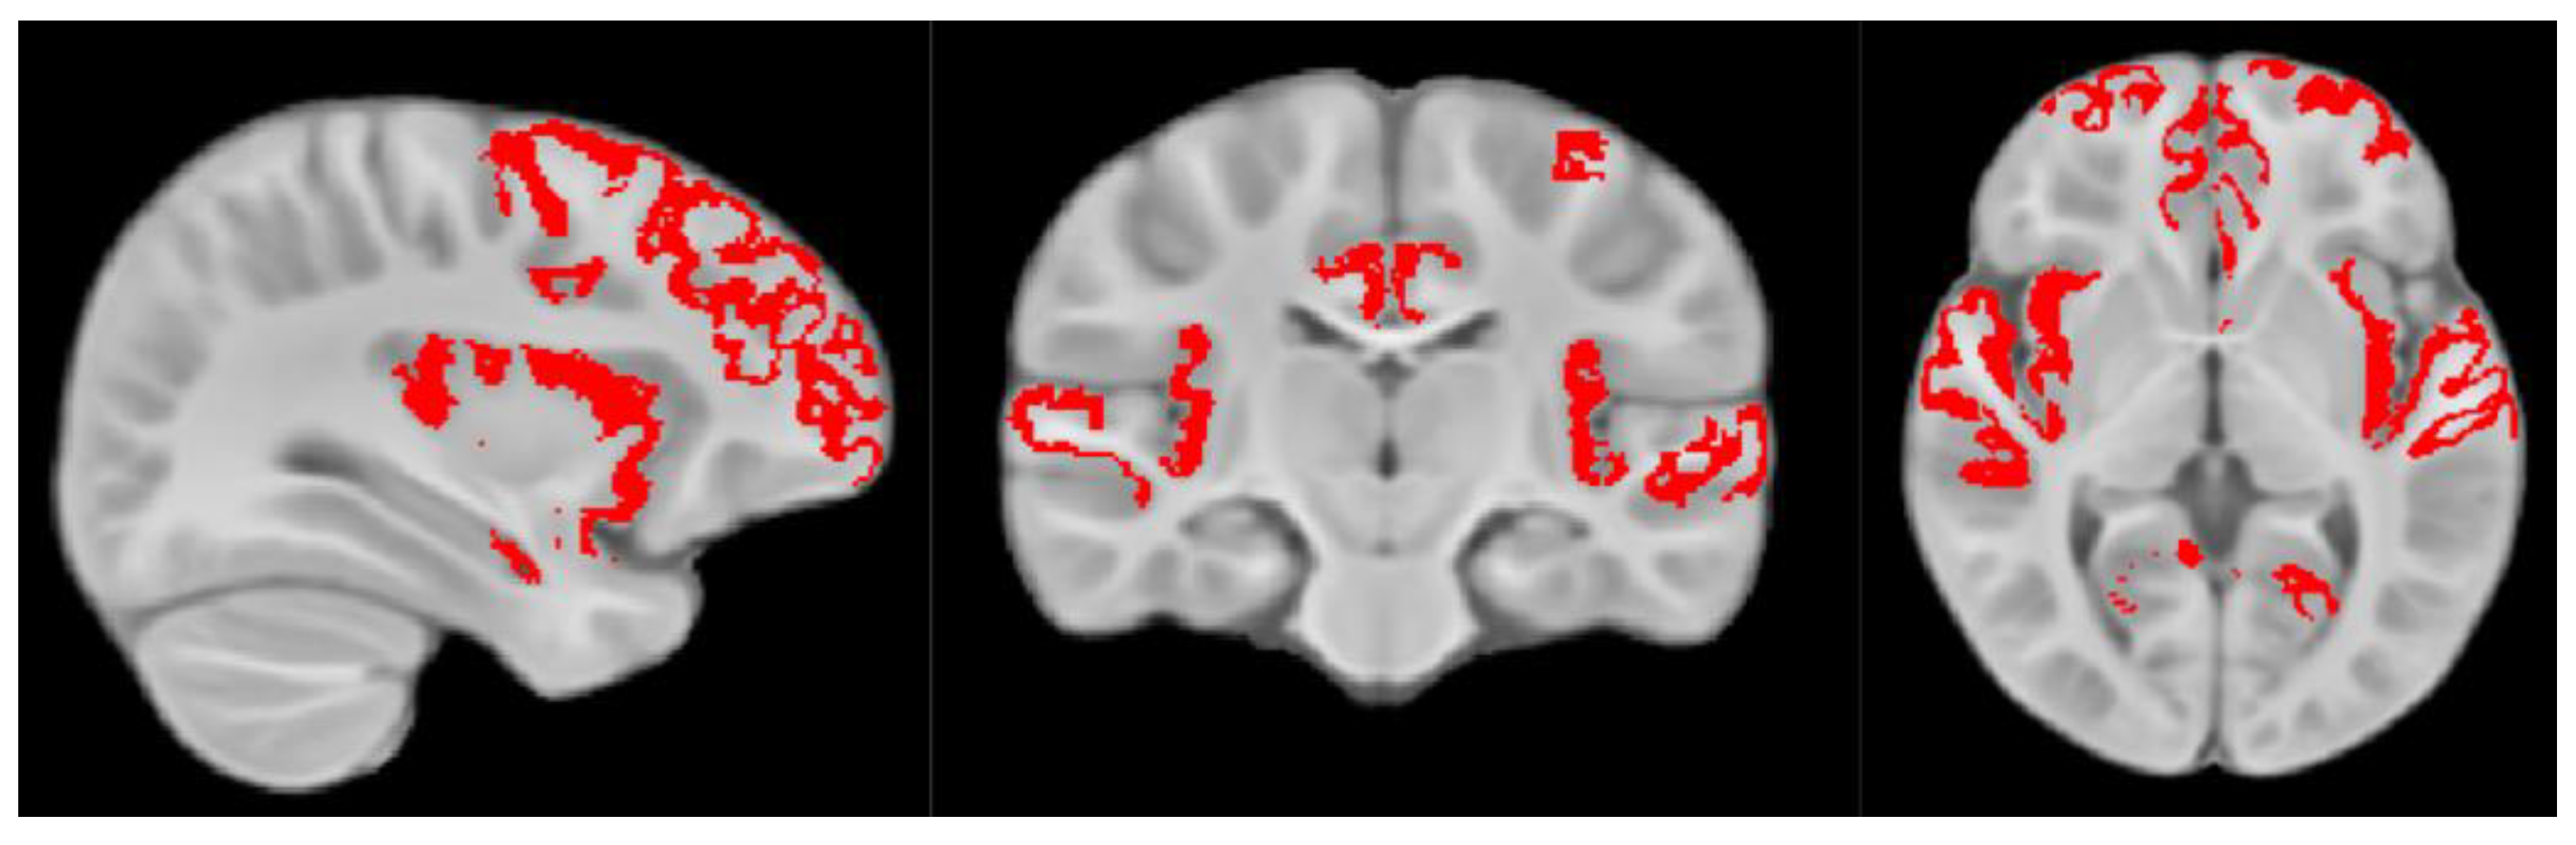

2.2. Myelin Magnetic Resonance Imaging (MRI) Data Acquisition and Processing

- Schneider, N.; Greenstreet, E.; Deoni, S.C.L. Connecting inside out: Development of the social brain in infants and toddlers with a focus on myelination as a marker of brain maturation. Child Dev. 2022, 93, 359–371. [Google Scholar] [CrossRef]